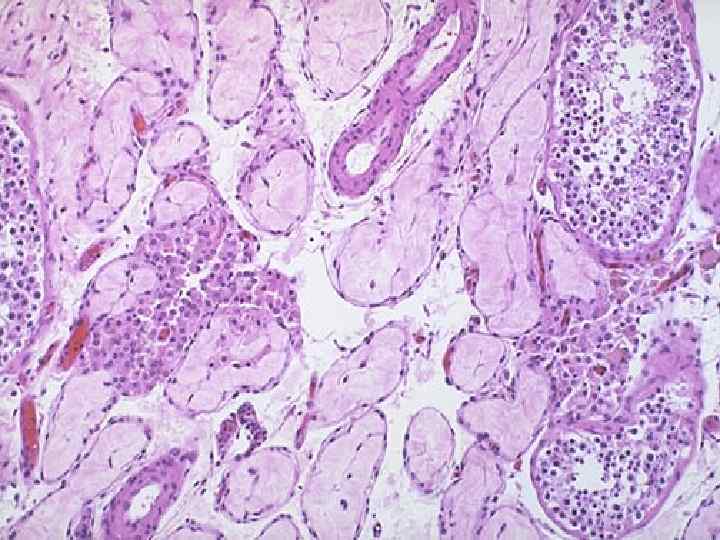

ДГПЖ